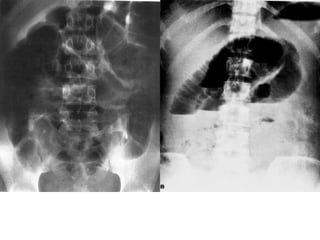

*Daáu hieäu: daõn, tröôùng hôi vaø dòch

1. Ruoät non > 3cm

2. Ruoät giaø > 6cm, manh traøng > 8cm

3. Möïc nöôùc – hôi ( xuaát hieän töø 12-24giôø)

4. Thaønh ruoät phuø neà ( >3mm)

5. OÅ buïng môø (dòch trong oå buïng)

 Phaân loaïi

1. Theo vò trí: ruoät non, ruoät giaø

2. Theo nguyeân nhaân: taéc ruoät cô naêng , taéc ruoät

cô hoïc.

- Taéc ruoät cô naêng : lieät ruoät

- Taéc ruoät cô hoïc : taéc ruoät do bít, do thaét